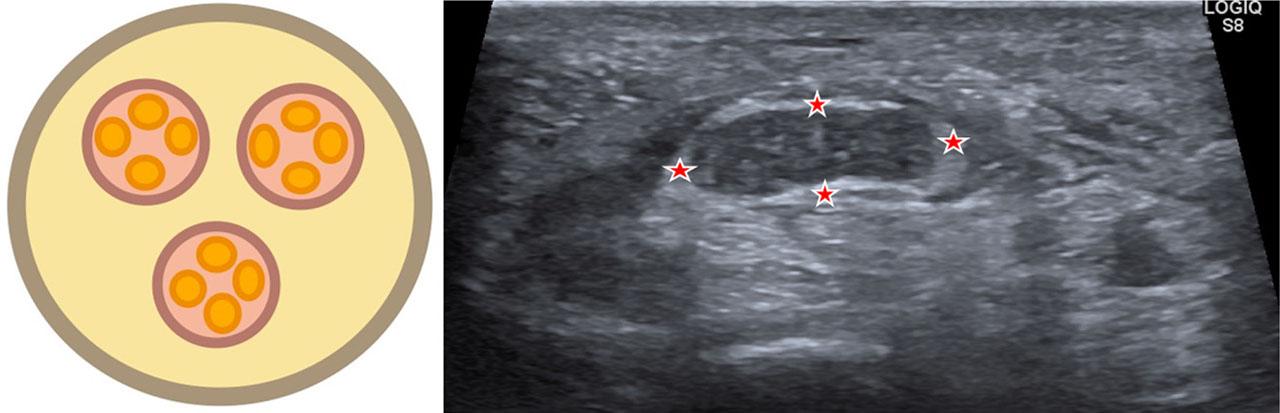

Normal nerves on ultrasound show hypoechoic fascicles surrounded by an outer sheath of bright epineurium and echogenic perineurium enveloping the fascicles. In cross-section, this creates the classic honeycomb pattern that distinguishes nerves from adjacent tissues (Fig. 1).

Schematic diagram illustrating the honeycomb architecture of nerves when imaged in cross-section (yellow – epineurium; purple – perineurium; orange – endoneurium). The image on the right shows the normal honeycomb architecture of the median nerve (asterisk) with an echogenic epineurium